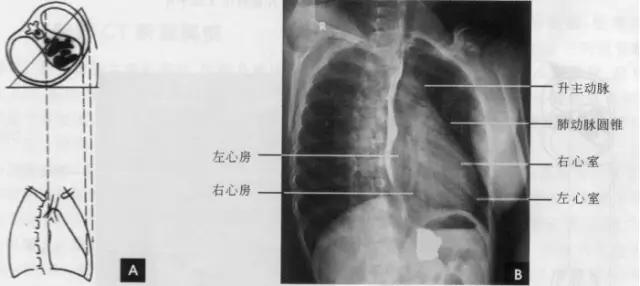

(一)后前位 正常心影2/3位于中线左侧,1/3位于右侧,心尖指向左下,心底部朝向右后上方,形成斜的纵轴。后前位心脏大血管有左右两缘:心右缘分为两段,上段为升主动脉与上腔静脉的总合影,在幼年和青年人边缘主要为上腔静脉影向上延伸,在老年人常见纡曲延长的升主动脉影突出于上腔静脉边缘之外;心右缘下段为右心房所构成,有时在心瞩角内可见一向外下方倾斜的三角形影,为下腔静脉攻肝静脉影,深吸气时明显。心左缘分为三段,上段为主动脉弓;中段为肺动脉主干,但偶尔可为左稀动脉构成,称肺动脉段或心腰,此段较低平或稍突出:下段由左心室构成,左心室在下方形成心尖。左心室与肺动脉之间有长约10cm的一小段,由左心耳构成,正常时不能与左心室区分。透视下左心室与肺动脉段的搏动方向相反,两者的交点称相反搏动点,该点上下两侧心缘里“翘翘板”样运动,该点位置是衡量左右心室增大的一个重要标志。肥胖人左心膈角常有脂肪垫充填,为密度较低的软组织影。后前位能了解心胸及肺循环概况,正常人心(h1+h2)胸(t)比率不大于0.5(如下图)。

(右前斜位)

标准右前斜位(又称第一斜位)为后前位向左旋转约45。所得影像。心前缘自上而下由主动脉弓曼升主动脉、肺动脉、右心室漏斗部、右心室前壁和左心室下端构成。升主动脉前缘平直,弓部则在上方弯向后行;肺动脉段和漏斗部稍为隆起;心尖以上大部分为右心室构成。心前缘与胸壁之间有尖向下的三角形透明区称为心前间隙。心后缘上段为左心房,下段为右心房,两者无清楚分界。心后缘与脊柱之间透明区称心后间隙,食管在心后间隙通过,钡剂充盈时显影。右前斜位主要观察右室流出道及左心房大小(如下图)。